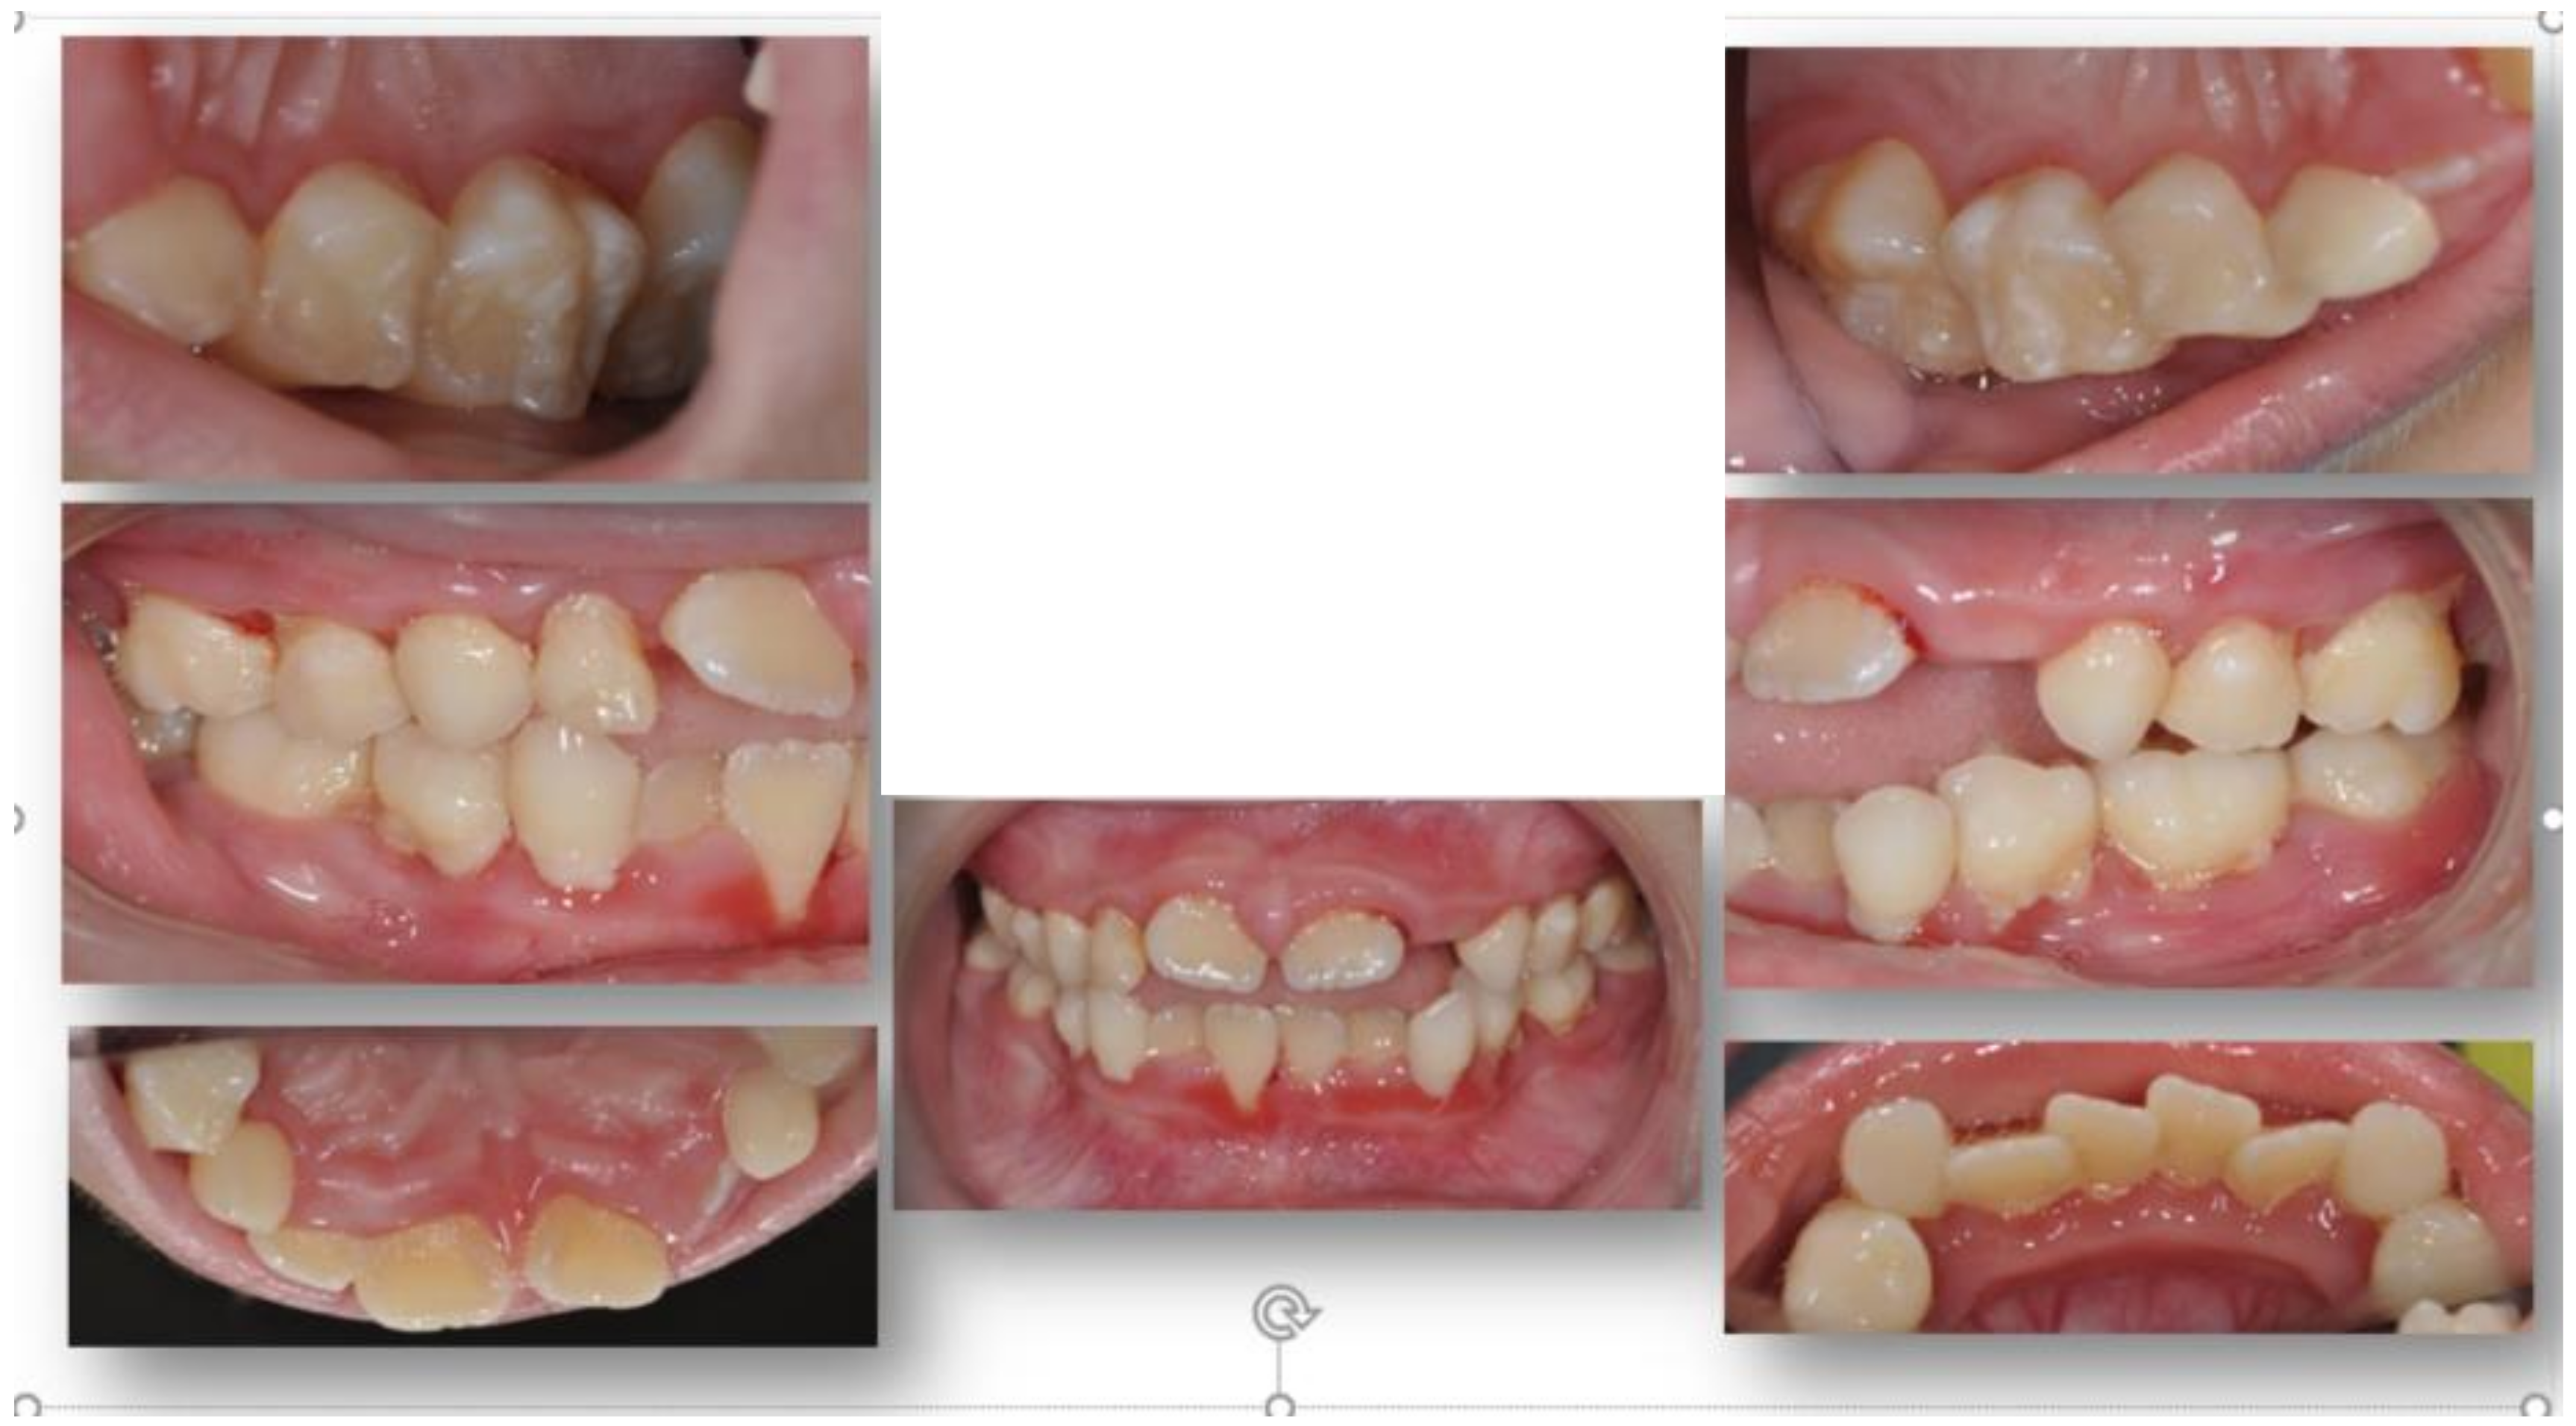

2. Case Presentation